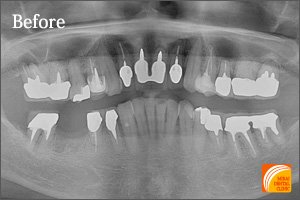

Before

期間 :3カ月

回数 :6回

費用 :766,800円

内容 :インプラント2本、外科用ステント、セラミック冠3本分含む

After

左下奥3本を失われた患者さんです。3本歯がないからといって3本インプラントが必要なわけではありません。2本インプラントを埋入することにより3本の歯を支えるインプラントブリッジにより治療しました。